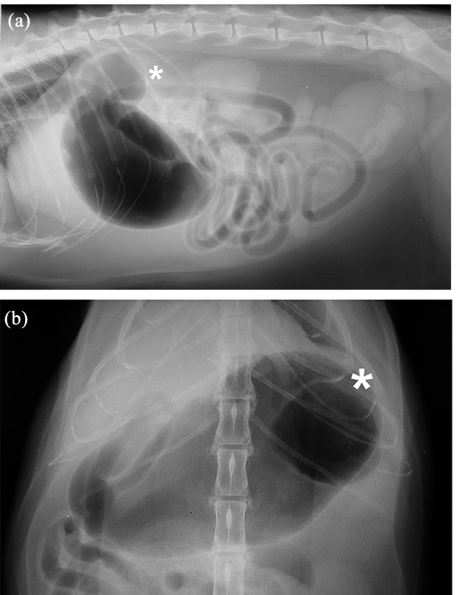

위게실의 경우 주증은 예상대로 구토, 식욕부진, 체중 감소가 주증으로 방사선 검사에서

이런 양상으로 GDV하고는 다른 양상의 공기주머니가 이중으로 있는 특징을 보인다.

당연하겠지만 이렇게 위내 gas가 충진되어 있지 않다면 진단하기 어려울 것이다.